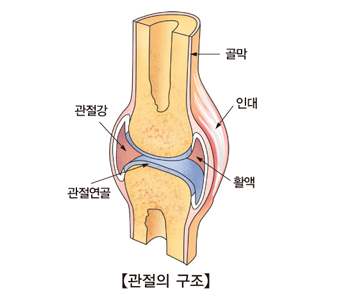

관절의 구조

관절을 둘러싸고 있는 구조는 크게 근육, 힘줄, 인대, 활막, 관절주머니, 연골 등으로 나눌 수 있습니다.

근육

관절을 지탱하고 움직일 수 있게 힘을 제공해줍니다.

힘줄

뼈와 근육을 연결해줍니다.

활막

활액을 분비하여 뼈와 뼈 사이의 마찰을 줄여줍니다.

관절주머니

윤활막을 둘러싼 주머니를 말하며 마찰을 감소시켜줍니다.

연골

뼈의 끝에 존재하며 무게를 지탱할 수 있게 하고 마찰을 감소시켜줍니다.